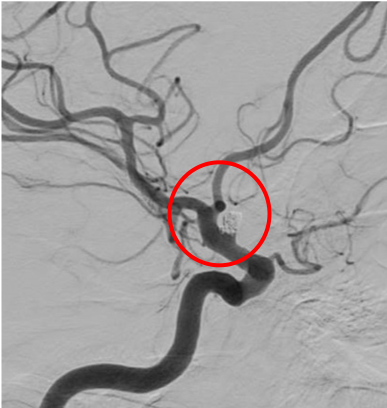

中大脳動脈瘤

術前の造影写真です。〇内に脳動脈瘤が造影されています。

術後の造影写真です。主幹動脈は温存できており、動脈瘤は造影されなくなっています。